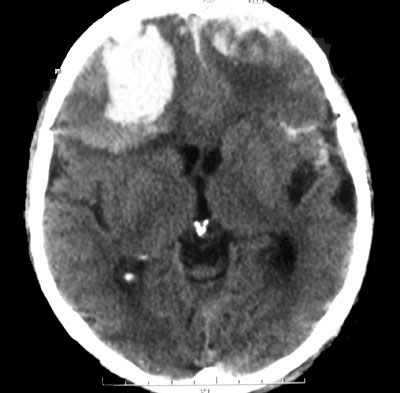

Внутричерепная гипотензия: КТ-исследования и их интерпретация

Раздел: Образы вокруг